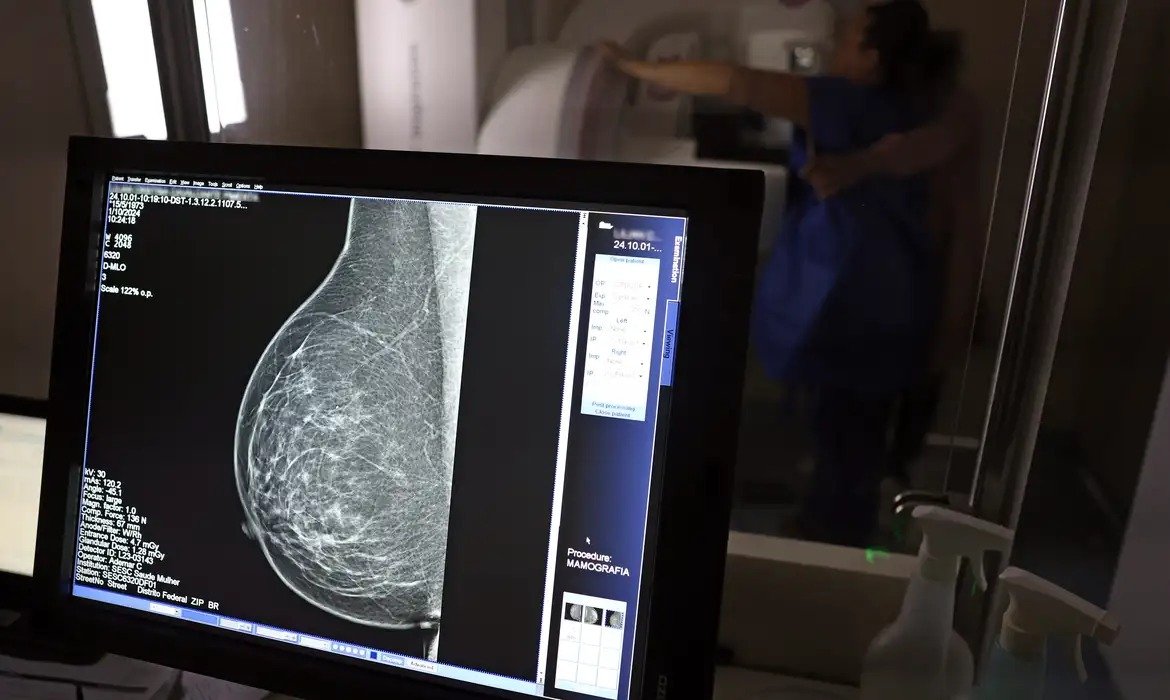

Ministério da Saúde passa a recomendar mamografia a partir dos 40 anos

Faixa de 40 a 49 anos concentra 23% dos casos de câncer de mama

Até então, a orientação era que o exame fosse feito a partir dos 50 anos.

A medida faz parte de um conjunto de ações anunciadas nesta terça-feira (23) voltado para a melhoria do diagnóstico e da assistência. A recomendação para mulheres a partir dos 40 anos é que o exame seja feito sob demanda, em decisão conjunta com o profissional de saúde.

As mamografias via SUS em pacientes com menos de 50 anos, de acordo com a pasta, representam 30% do total, o equivalente a mais de 1 milhão apenas no ano de 2024.

Outra medida anunciada é a ampliação da faixa etária para o rastreamento ativo – quando a mamografia é solicitada de forma preventiva a cada dois anos. A idade limite, até então, era 69 anos. Agora, passa a ser 74 anos. Dados do ministério revelam que quase 60% dos casos de câncer de mama estão concentrados entre 50 e 74 anos.

Os números mostram que, em 2024, cerca de 4 milhões de mamografias para rastreamento e 376,7 mil exames diagnósticos foram realizados no SUS.